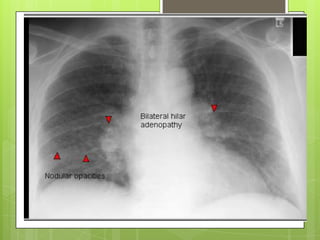

CLÍNICA  Datos clínicosno son específicos.  Formas leves no causan síntomas  En etapas avanzadas: tos (primero) y disnea Rx tórax:  Formas simples nódulos redondeados densos de 1.5-10 mm en campos pulmonares superiores  Formas complicadas: lesiones > 10 mm en uno a dos tercios del pulmón. Calcificación de ganglios en “cascara de huevo” ocurre en 5%

DIAGNÓSTICO  Exposición laboral>5 años  Radiografía con imágenes compatibles

DIAGNÓSTICOS DIFERENCIALES  Linfangitiscarcinomatosa  Histoplasmosis  TB miliar  Neumonía por varicela  Hemosiderosis  Sarcoidosis  Proteinosis alveolar